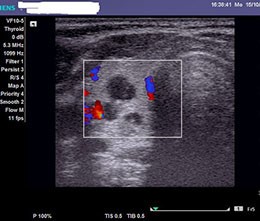

Диагностика

Диагностика данного заболевания осуществляется с помощью УЗИ метода, который позволяет достаточно быстро определить наличие деформации желчного пузыря и утолщение стенок, в отличие от метода компьютерной томографии, при котором данная патология не обнаруживается. Исследование является безвредным, причем доктор-диагност принимает непосредственное участие в получении изображения, что имеет как положительные, так и отрицательные стороны.

Плюсом считается возможность проведения более подробного исследования объекта. Минус в том, что расшифровка изображения зависит от опытности доктора и правильности использования методик. Считается, что УЗИ двигательных нарушений желчного пузыря – наиболее трудоемкий процесс.